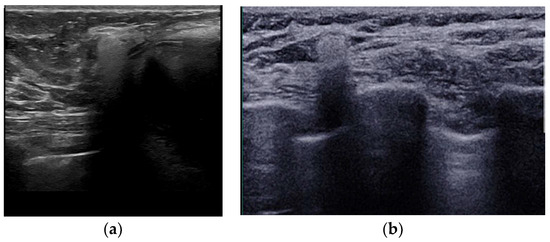

- Seiler, S.J.; Sharma, P.B.; Hayes, J.C.; Ganti, R.; Mootz, A.R.; Eads, E.D.; Teotia, S.S.; Evans, W.P. Multimodality Imaging-based Evaluation of Single-Lumen Silicone Breast Implants for Rupture. Radiographics 2017, 37, 366–382. [Google Scholar] [CrossRef] [PubMed]

- Ahn, C.Y.; DeBruhl, N.D.; Gorczyca, D.P.; Shaw, W.W.; Bassett, L.W. Comparative silicone breast implant evaluation using mammography, sonography, and magnetic resonance imaging: Experience with 59 implants. Plast. Reconstr. Surg. 1994, 94, 620–627. [Google Scholar] [CrossRef] [PubMed]

- Ikeda, D.M.; Borofsky, H.B.; Herfkens, R.J.; Sawyer-Glover, A.M.; Birdwell, R.L.; Glover, G.H. Silicone breast implant rupture: Pitfalls of magnetic resonance imaging and relative efficacies of magnetic resonance, mammography, and ultrasound. Plast. Reconstr. Surg. 1999, 104, 2054–2062. [Google Scholar] [CrossRef] [PubMed]

- O’Toole, M.; Caskey, C.I. Imaging spectrum of breast implant complications: Mammography, ultrasound, and magnetic resonance imaging. Semin. Ultrasound CT MRI 2000, 21, 351–361. [Google Scholar] [CrossRef] [PubMed]

- Salzman, M.J. Silent Rupture of Silicone Gel Breast Implants: High-Resolution Ultrasound Scans and Surveys of 584 Women. Plast. Reconstr. Surg. 2022, 149, 7–14. [Google Scholar] [CrossRef]

- Goldammer, F.; Pinsolle, V.; Dissaux, C.; Pelissier, P. Accuracy of mammography, sonography and magnetic resonance imaging for detecting silicone breast implant ruptures: A retrospective observational study of 367 cases. Ann. Chir. Plast. Esthet. 2021, 66, 25–41. [Google Scholar] [CrossRef]

- Rochira, D.; Cavalcanti, P.; Ottaviani, A.; Tambasco, D. Longitudinal Ultrasound Study of Breast Implant Rupture Over a Six-Year Interval. Ann. Plast. Surg. 2016, 76, 150–154. [Google Scholar] [CrossRef]

| Possible rupture | Keyhole or teardrop Sign | Focal silicone invagination between implant shell and fibrous capsule |

| Salad-oil sign Rat-tail sign | Silicone gel mixed with peri-implant fluid Contour irregularity extending along the chest wall | |

| Pitfalls | Complex radial folds | Long invaginations of the shell |

| Gel bleed | Silicone within the axillary lymph nodes | |